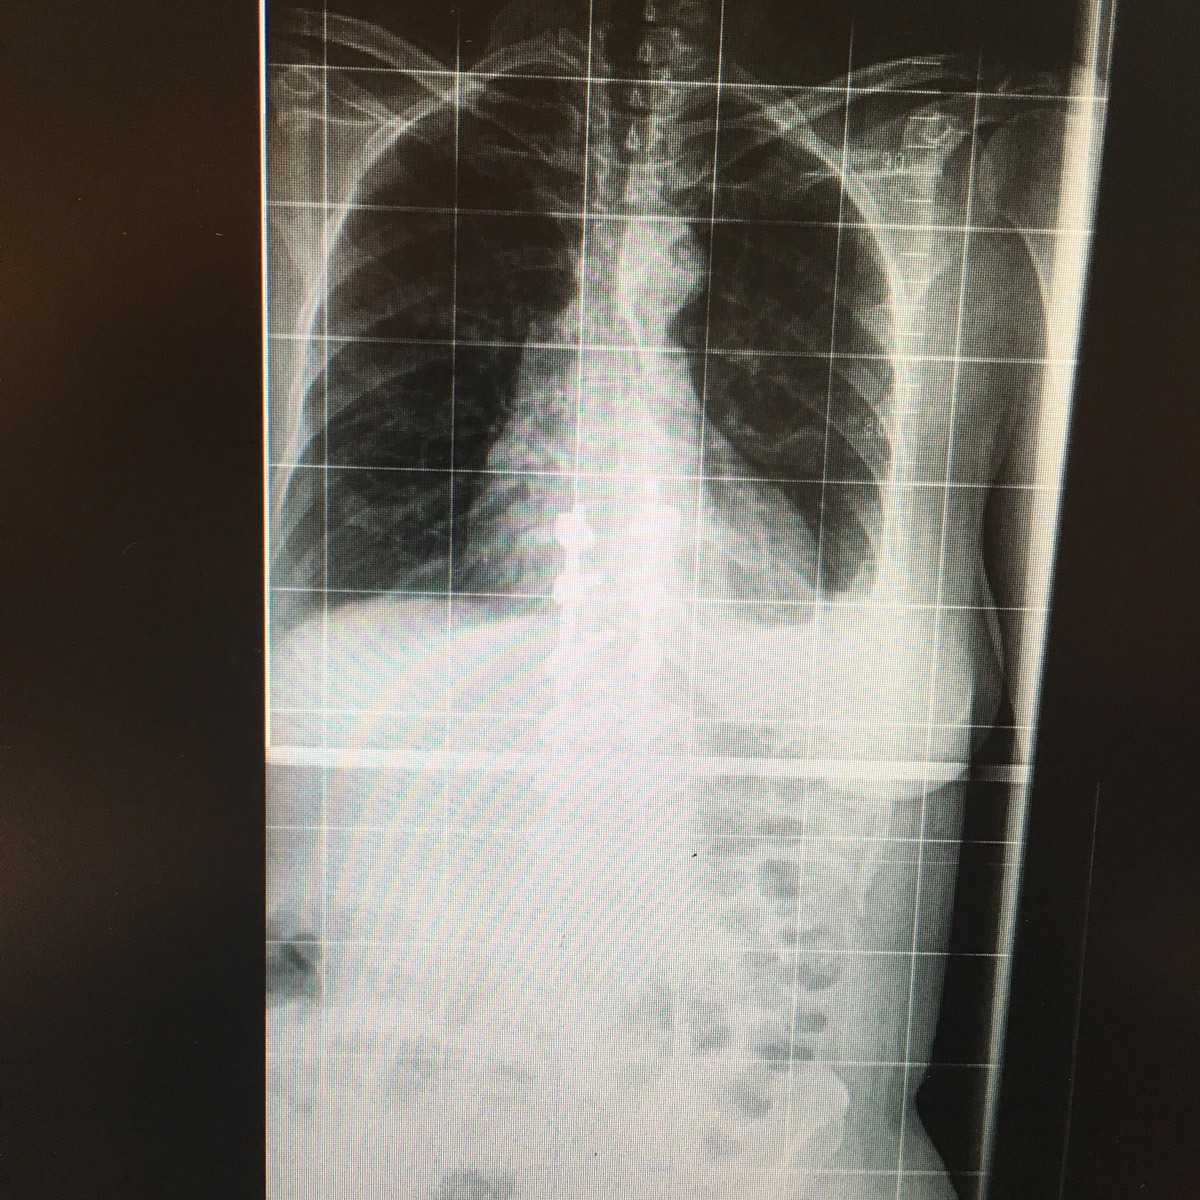

Εικ 3: Μετεγχειρητική ακτινογραφία της Σπονδυλικής Στήλης α) Προσθιοπισθία β) Πλαγία σε όρθια στάση

Παρατηρείται: 1) Σημαντική διόρθωση της θωρακο-οσφυϊκής σκολίωσης, 2) Έκταση της σπονδυλοδεσίας στην περιοχή από τον 9ο θωρακικό έως τον 4ο οσφυϊκό σπόνδυλο, 3) Θωρακική κύφωση εντοπιζομένη κυρίως στη μετάπτωση μεταξύ της σπονδυλοδεσίας και την ανώτερης θωρακικής μοίρας της σπονδυλικής στήλης.